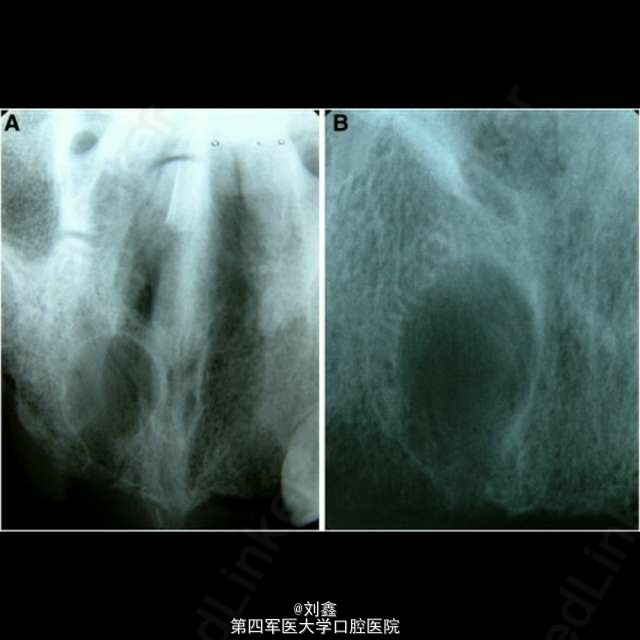

患者男, 59 岁,因曲面断层片显示上颌前部见一单房透亮影像来诊,行囊肿切除活检术,病理结果显示为表皮样囊肿。 表皮样囊肿是一种可发生在全身任何部位的良性软组织瘤样病变,男性多见,青春期前出现需考虑 Gardner 综合征。病变多局限、单个。主要病因为局部毛囊炎症,以及上皮愈合过程中毛囊漏斗部的增生及创伤性的上皮植入。影像学见单房透射影还需结合病史、检查等鉴别诊断根侧牙周囊肿、角化囊肿、球上颌囊肿、创伤性骨囊肿、成釉细胞瘤等。组织学鉴别应排除皮炎囊肿,皮样囊肿中可见皮肤附件如毛囊、皮脂腺、汗腺等。普遍认为病因包括先天性及创伤性,但有证据显示深入到颅骨等硬组织引起囊性扩张的病变多由于创伤性植入。表皮样囊肿预后良好,治疗可行保守的手术切除。